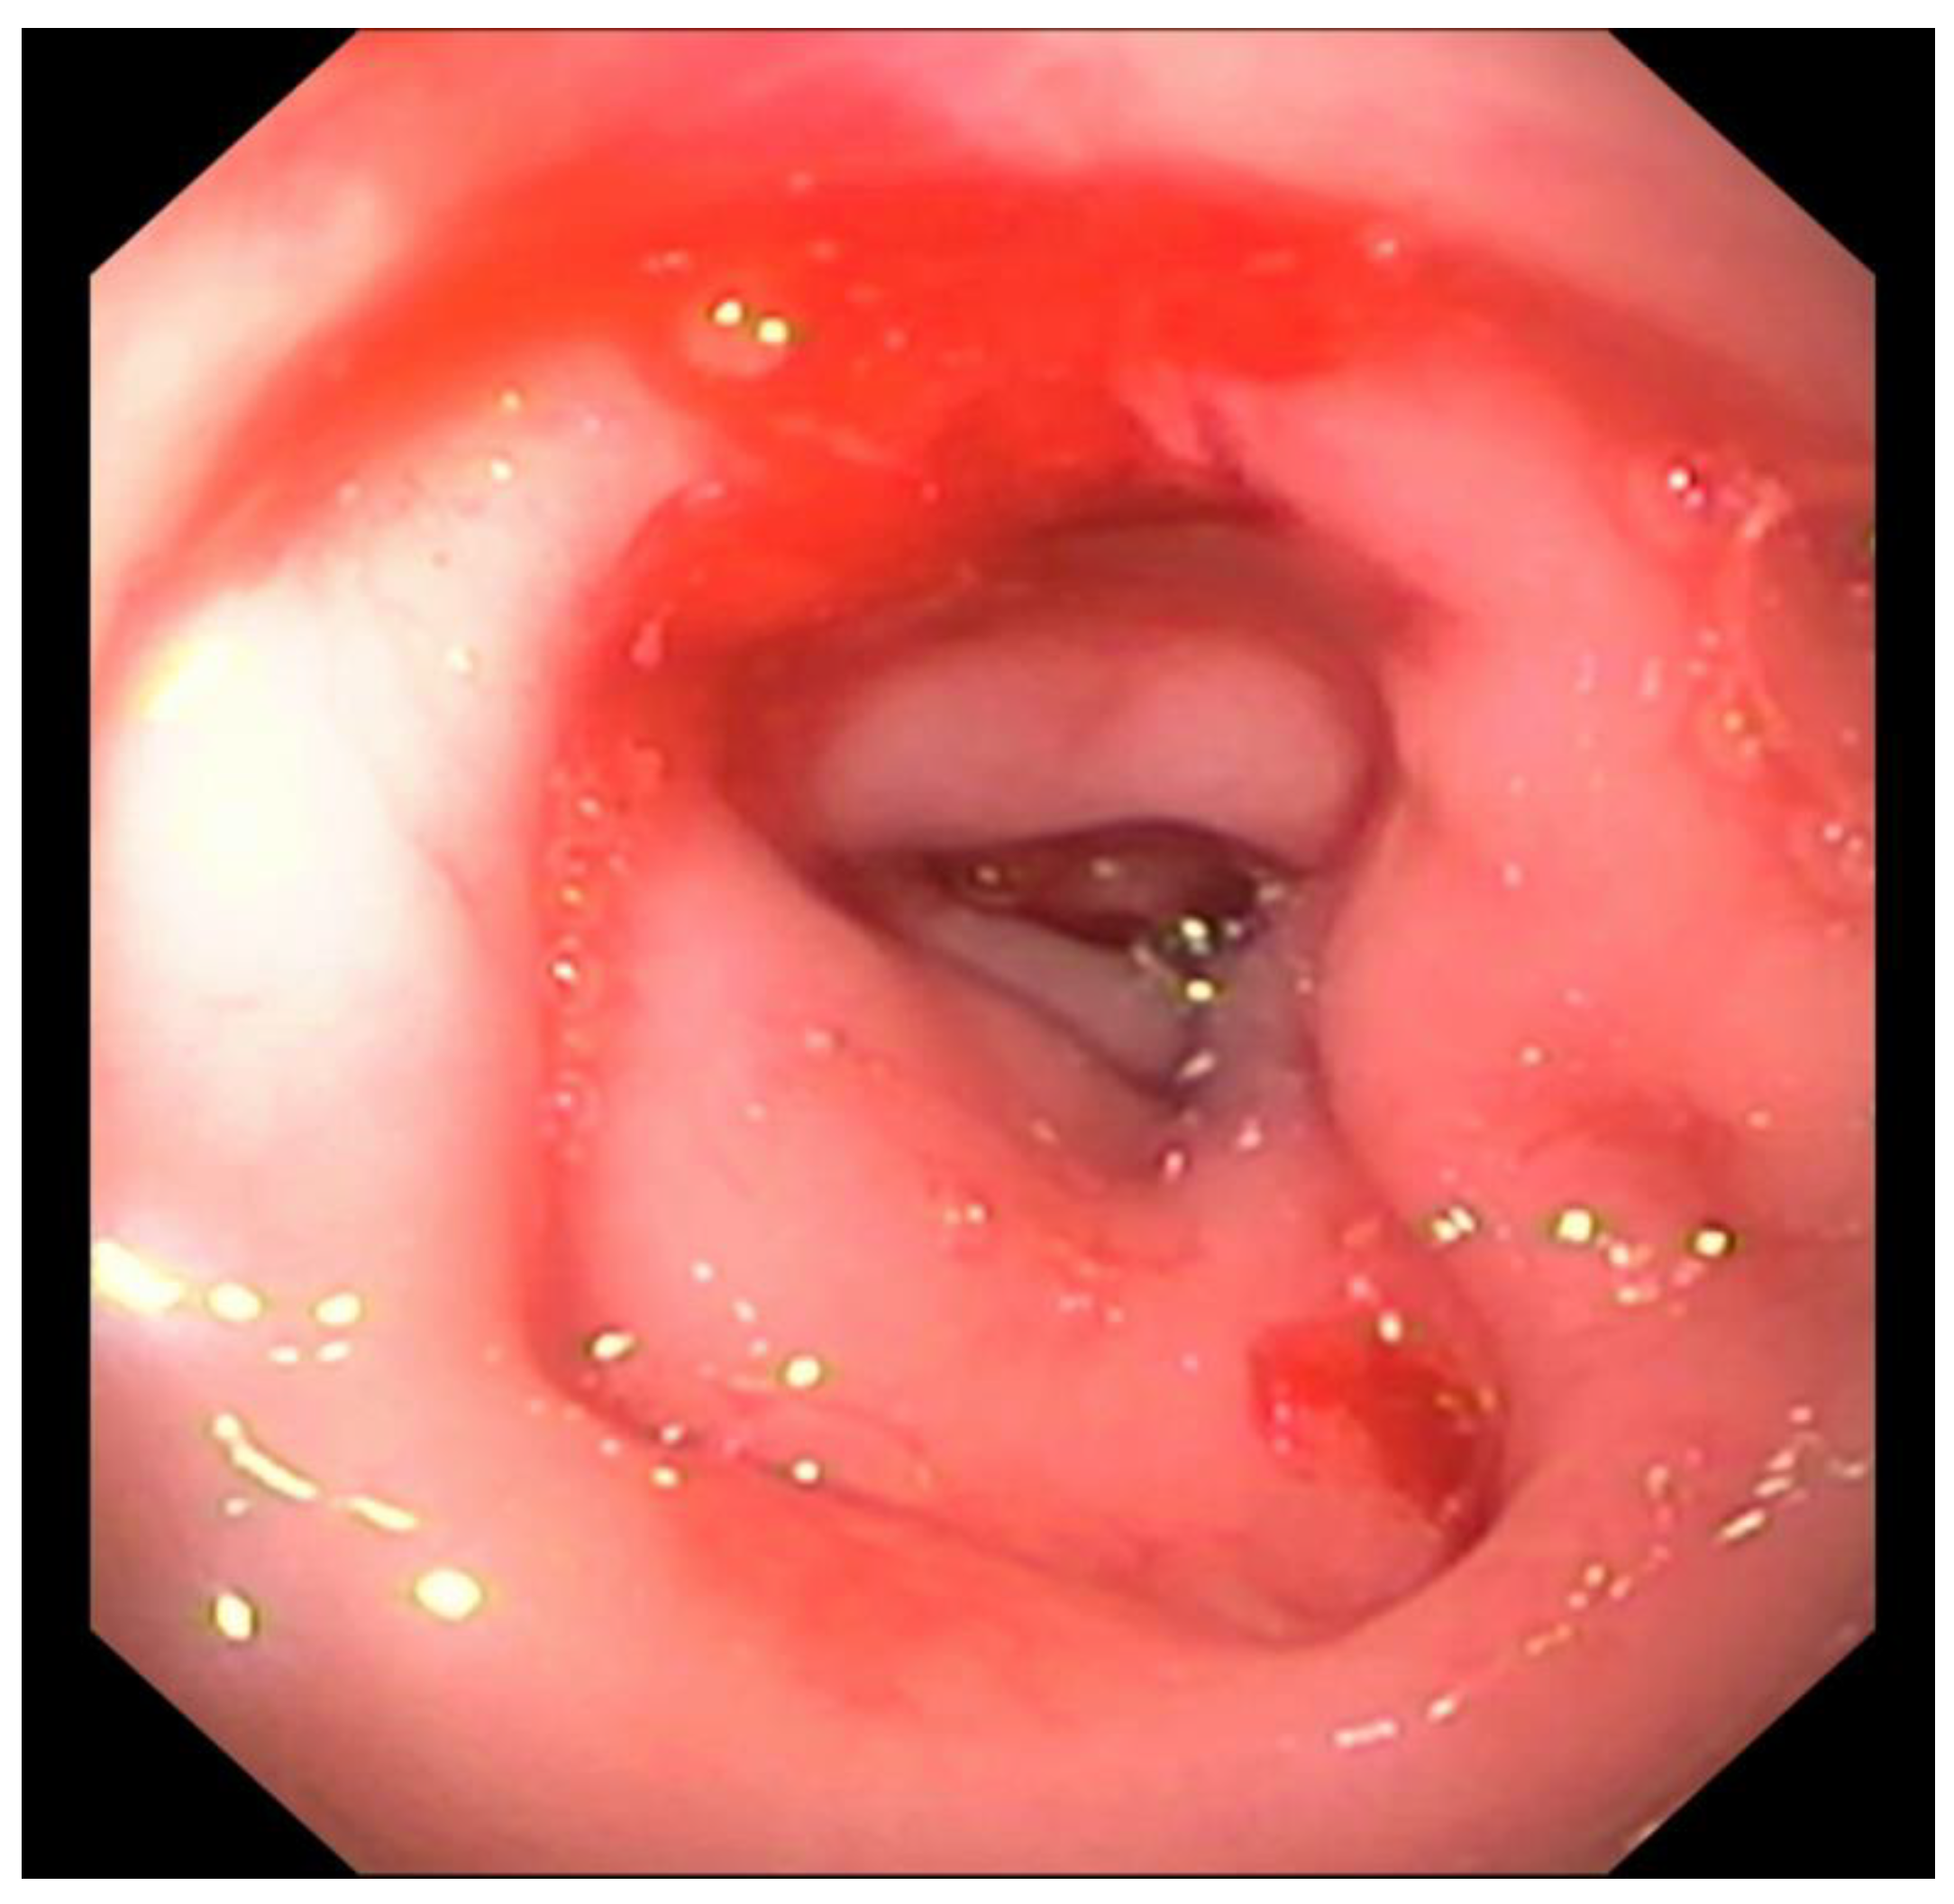

Endoscopic abnormalities are presented in Table 6 and included: gaping, atone and opened ileocolic junction in 8 cases (4 in group A and 4 in group B, Figure 5), absence of cecum in one case, colonic stenosis of variable degree in 12 cases (2 in group B and 10 in group A, Figure 6), erosive or marked macroscopic signs of colopathy in 5 cases (5 in group B and 3 in group A), non-specific slight to moderate signs of colopathy in 8 cases (3 in group B and 5 in group A) and unremarkable colon in two cases (one in group A and B).

Colonoscopy allowed the diagnosis in most cases. Partial colonic agenesis was associated with other anatomical malformation in 8 cases and included absence of the cecum or abnormal ileocolic junction (Image 3). Focal stenosis was also identified in 12 cases. Marked macroscopic signs of active colonic disease were identified in 5 cases and corresponded to a diagnosis of granulomatous inflammation or IBD. In most cases however, the colic mucosa was macroscopically normal or only slightly modified, especially in group A.

Figure 5. Abnormal ileocolic junction in a cat (Case 10).